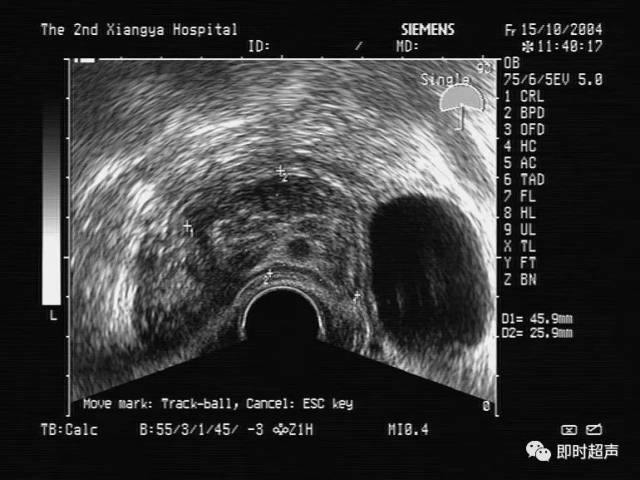

【推荐】妇科疾病超声诊断(下)

妇科做检查阴超

经阴超检查

妇科阴超检查什么